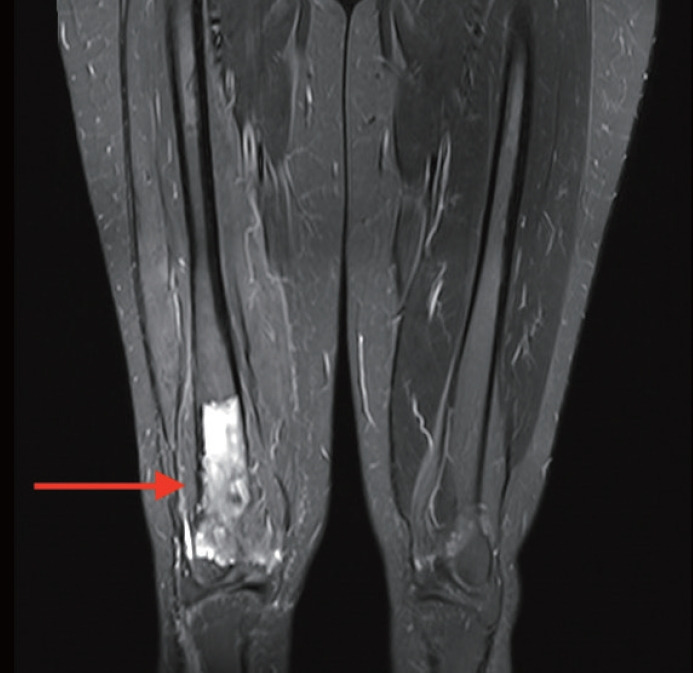

原发性骨细肌肉瘤非常罕见。从组织学上看,它与软组织的良性肌肉瘤相似。鉴于这种肿瘤的罕见性,只有在临床研究和检查排除了其他部位的转移后才能做出诊断。在此,我们又描述了一例原发性骨亮肌肉瘤。我们报告了一名 32 岁的女性患者,她因右膝关节疼痛就诊,影像学检查发现其右股骨远端肿块。活组织检查显示,肿瘤由纺锤形细胞束组成,呈不同形态排列,多形性明显。肿瘤细胞的平滑肌肌动蛋白呈阳性,desmin 和 H-caldesmon 阳性。影像学检查未发现体内有其他肿块。诊断结果为骨小梁肉瘤。鉴于原发性骨细肌肉瘤的诊断鉴别范围很广,因此了解这种罕见的骨肿瘤表型及其组织形态学和免疫组化特征对于准确诊断非常重要。

Primary leiomyosarcoma of the bone is rare. Histologically, it resembles leiomyosarcoma of soft tissue. Given the rarity of this entity, its diagnosis should be made only after clinical studies and workup have excluded metastasis from other sites. Herein, we describe an additional case of primary bone leiomyosarcoma. We report a 32-year-old female patient, who presented with right knee pain and was found to have a right distal femur mass by imaging studies. Biopsy showed a neoplasm composed of fascicles of spindle cells, arranged in different patterns, with significant pleomorphism. The tumor cells were positive for smooth muscle actin, focally positive for desmin and H-caldesmon. No other masses in the body were detected by imaging studies. The diagnosis of leiomyosarcoma of the bone was rendered. Given the broad diagnostic differential of primary bone leiomyosarcoma, it is important to be aware of this rare bone tumor phenotype and of its histomorphologic and immunohistochemical features for an accurate diagnosis.